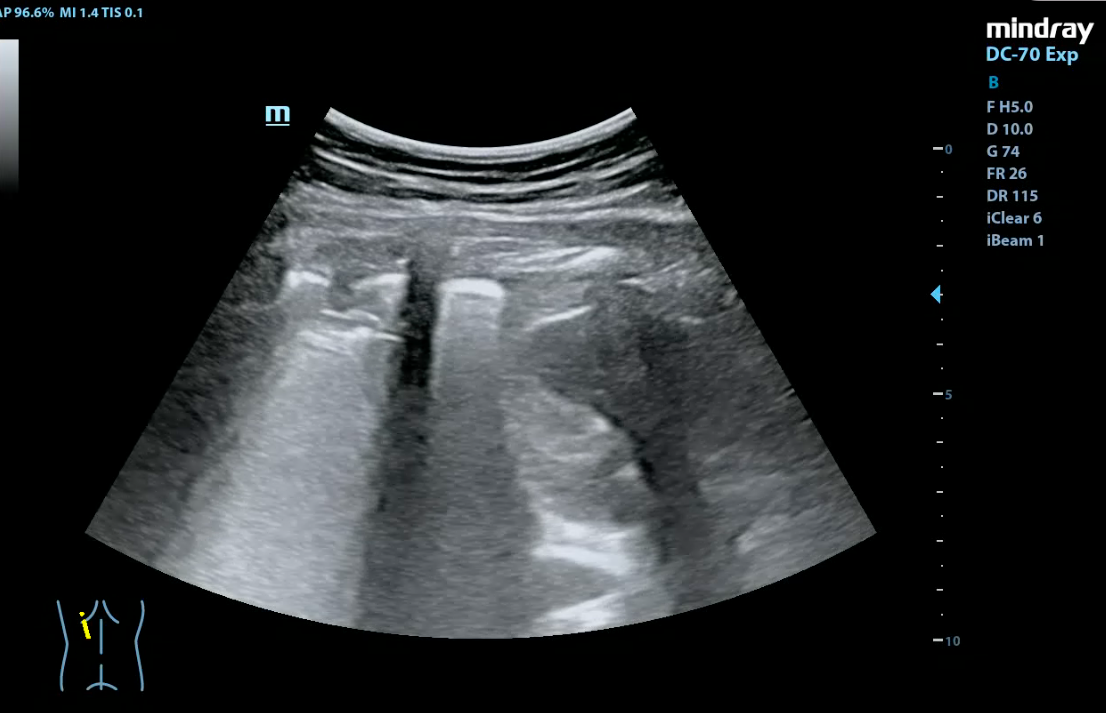

Paciente de 15 años con AP de asma y rinitis alérgica que acude al Servicio de Urgencias por fiebre de hasta 38,5 ºC y tos seca de 2 días de evolución. Además, refería dolor abdominal en hipocondrio izquierdo sin cambios en el hábito intestinal y sin vómitos. Dada la estabilidad del paciente y exploración física anodina se decide tratamiento sintomático en domicilio y revisión en consulta en días posteriores. Acude a la consulta tres días después refiriendo persistencia de la fiebre, disminución parcial de la ingesta y aumento de frecuencia de los accesos de tos seca. Exploramos al paciente: presenta crepitantes bibasales junto a algún roncus acentuado en base izquierda, se solicita una radiografía de tórax donde se objetiva una consolidación incipiente en la base pulmonar izquierda que borra mínimamente el reborde superior diafragmático. Debido a la alta incidencia de casos y clínica atípica compatible con infección por Mycoplasma se realiza un exudado resultando ser positivo, por lo que se pauta antibioterapia con Azitromicina durante 3 días. Tras haber cumplido con la pauta medicamentosa, acude nuevamente a consulta refiriendo picos febriles de hasta 40 ºC, malestar general, tos con expectoración y empeoramiento del dolor abdominal. Dado que a la auscultación y clínica presenta empeoramiento decidimos realizar una ecografía pulmonar para descartar complicaciones: se objetiva consolidación de ecogenicidad variable en su interior localizado en base pulmonar izquierda, con presencia de líneas B en el parénquima pulmonar sin presentar aparente derrame pleural.

Gracias a la ecografía se ha podido diagnosticar lo anterior sin irradiar nuevamente al paciente.

La ecografía pulmonar ha demostrado una alta precisión para el diagnóstico de neumonía siendo una prueba complementaria que no irradia al paciente. Podemos comenzar a implementarla tanto en la consulta como en los Servicios de Urgencias ofreciendo una respuesta inmediata a la pregunta asistencial y de esta manera, aumentar la capacidad resolutiva y diagnóstica de nuestros pacientes.